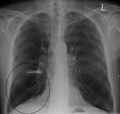

A chest X-ray and complete blood count may be useful to exclude other conditions at the time of diagnosis.[61] Characteristic signs on X-ray are overexpanded lungs, a flattened diaphragm, increased retrosternal airspace, and bullae while it can help exclude other lung diseases, such as pneumonia, pulmonary edema or a pneumothorax.[62] A high-resolution computed tomography scan of the chest may show the distribution of emphysema throughout the lungs and can also be useful to exclude other lung diseases.[15] Unless surgery is planned, however, this rarely affects management.[15] An analysis of arterial blood is used to determine the need for oxygen; this is recommended in those with an FEV1 less than 35% predicted, those with a peripheral oxygen saturation of less than 92% and those with symptoms of congestive heart failure.[14] In areas of the world where alpha-1 antitrypsin deficiency is common, people with COPD (particularly those below the age of 45 and with emphysema affecting the lower parts of the lungs) should be considered for testing.[14]

Chest X-ray demonstrating severe COPD. Note the small heart size in comparison to the lungs.